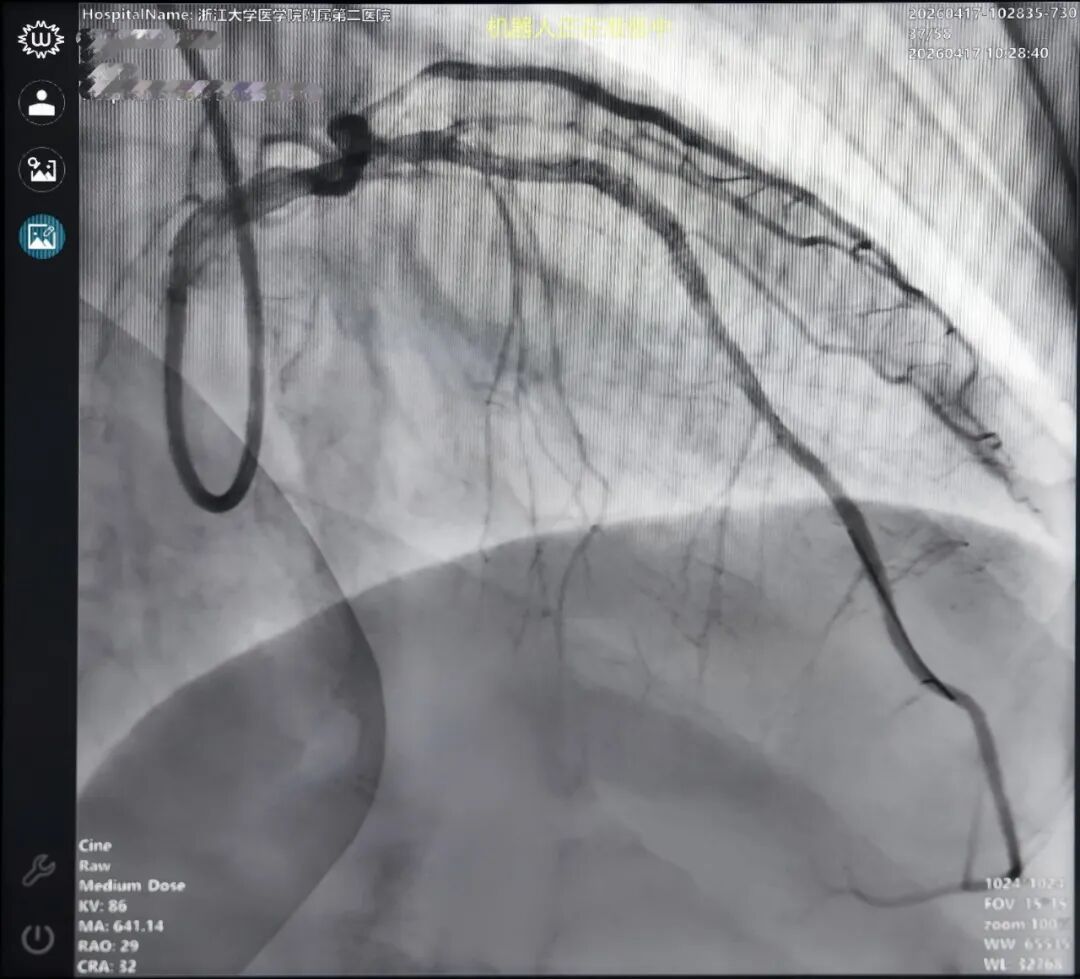

浙大二院术者为刘炳辰教授,病例为前降支近段95%狭窄,合并D1近段70%狭窄、回旋支中段次全闭塞、远段慢性闭塞及右冠近段60%狭窄,多支血管同时受累,整体呈长段弥漫病变特征。该类病例虽无严重钙化、复杂分叉或明显迂曲,但在多支病变背景下,对器械长距离递送的稳定性、连续操作的一致性,以及长病变处理过程中的节奏控制提出了更高要求。机器人完成IVUS引导下预扩、支架及后扩全流程,术后造影显示血管供血效果良好。